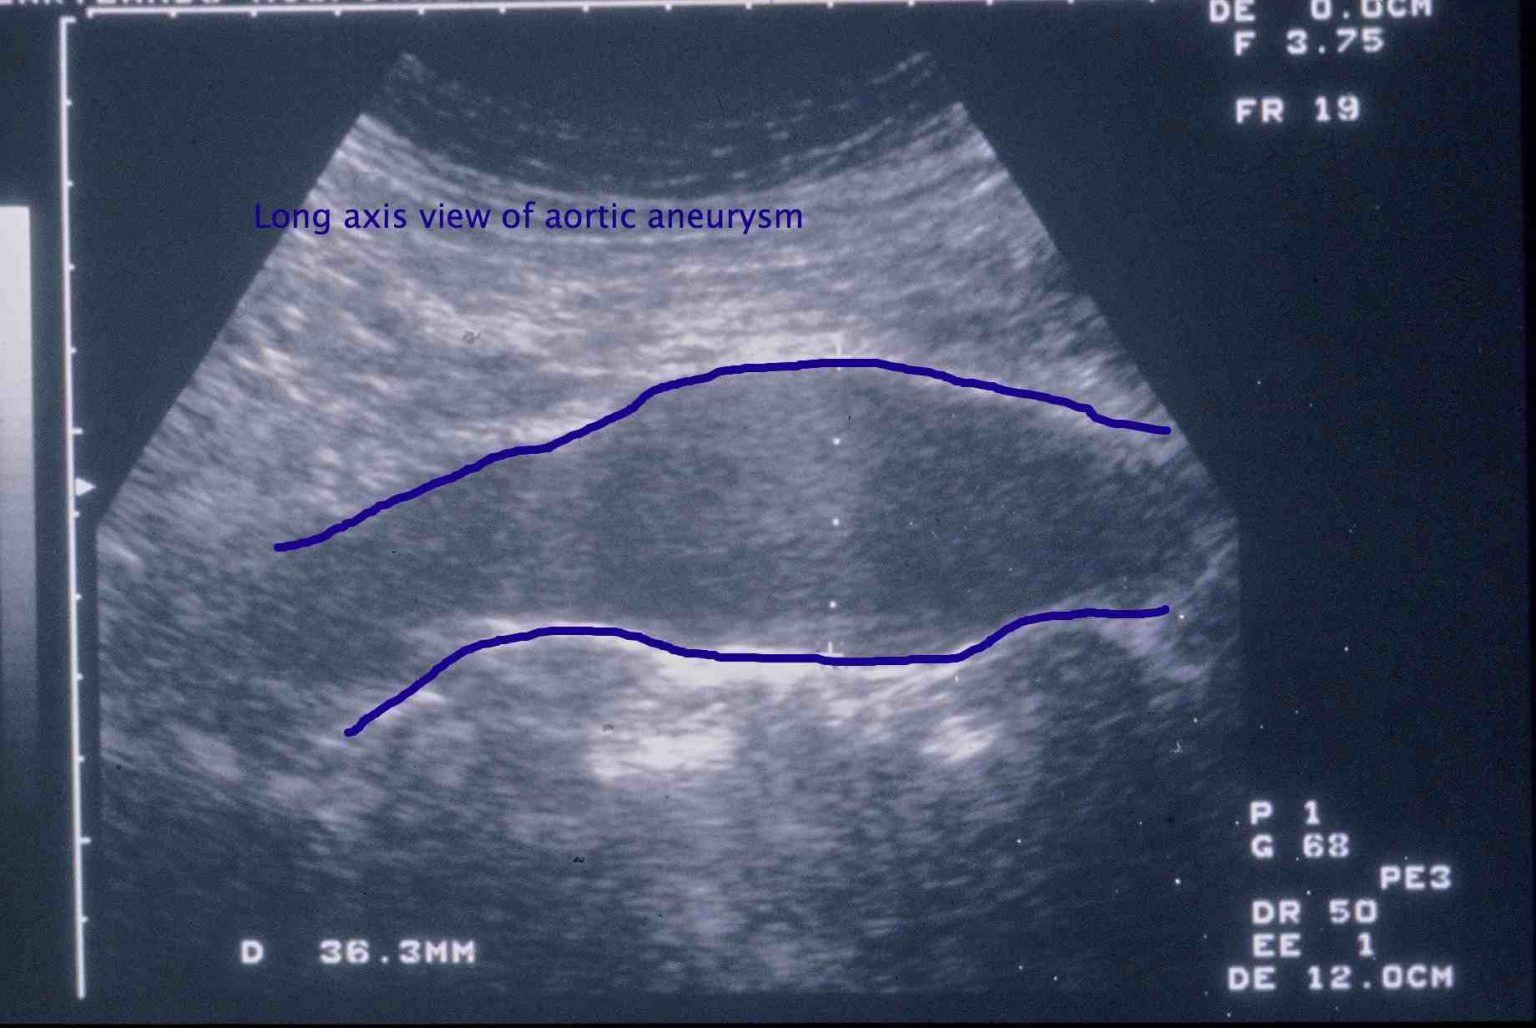

At present in New Zealand there is no screening programme. If a screening programme were to be developed it might work as described below. You would be invited to attend for a free ultrasound scan if you were a man between the ages of 65 and 74 yrs old. An ultrasound scan is a scan commonly used to examine the baby during pregnancy. It is safe and painless and usually will only take a few minutes to determine whether an AAA is present. Examples of ultrasound scans are shown in the black, white and blue images. Patients with a normal scan will not usually need any further follow up.